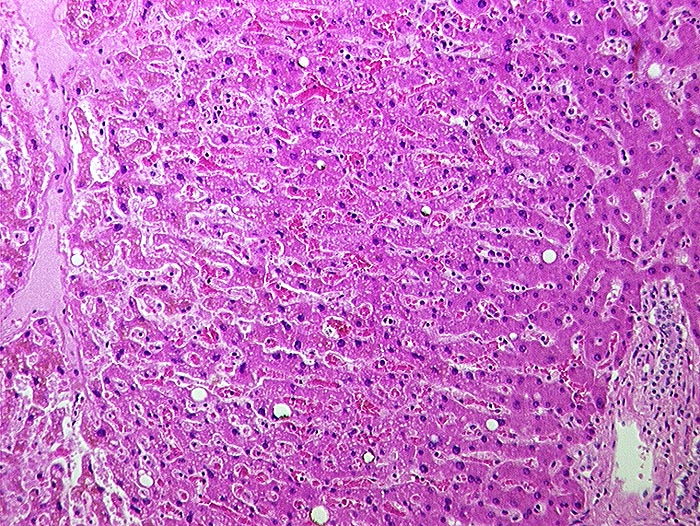

Subakute Stauung

vaskulär / Durchblutungsstörung

Leber

Links eine Zentralvene, rechts ein Portalfeld. Die Sinusoide sind vor allem um die Zentralvene erweitert und die Leberzellplatten leicht verschmälert (Druckatrophie).

In der Bindegewebsfärbung kein vermehrter Fasernachweis rund um die Zentralvene.

Histologie